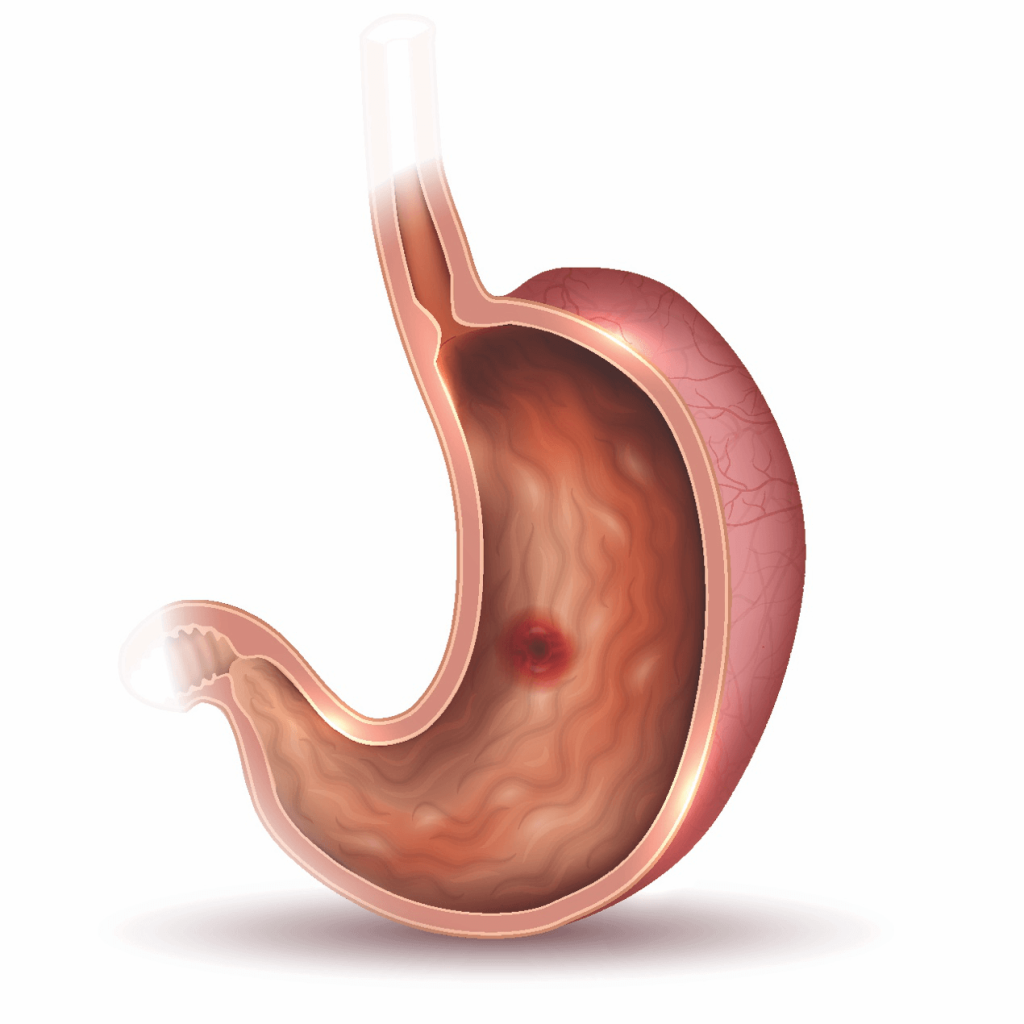

Gastrointestinal Bleeding

Gastrointestinal bleeding refers to bleeding that occurs in the digestive tract, affecting organs such as the esophagus, stomach, small intestine, or colon. This condition can range from mild to severe and may present as overt bleeding (visible in vomit or stool) or occult bleeding (not visible). Common causes of gastrointestinal bleeding include peptic ulcers, gastritis, diverticulosis, and colorectal polyps. Symptoms may include black or bloody stools, vomiting blood, weakness, and abdominal pain.